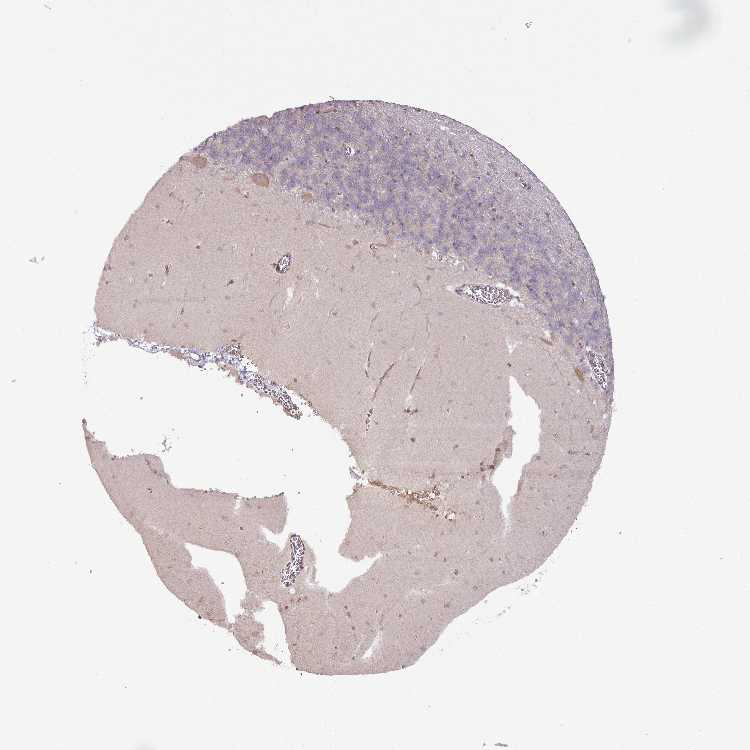

CEREBELLUM - Antibody stainingi

Antibody staining in the annotated cell types in the current human tissue is reported as not detected, low, medium, or high, based on conventional immunohistochemistry profiling in selected tissues. This score is based on the combination of the staining intensity and fraction of stained cells.

Each image is clickable and will lead to virtual microscopy that enables deeper exploration of all samples and also displays staining intensity scores, fraction scores and subcellular localization as well as patient and tissue information for each sample.

Antibody HPA053938

Purkinje cells Medium

Cells in granular layer Not detected

Cells in molecular layer Low